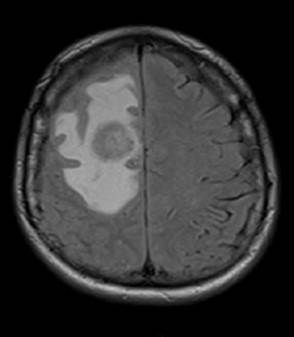

Se realizó una tomografía axial computarizada de cráneo simple que mostro área hipodensa con gran edema en región frontal derecha sin efecto de masa. De igual forma, se practicó una resonancia magnética nuclear cerebral que evidenció una pequeña lesión nodular aislada en cabeza del núcleo caudado izquierdo y cortico subcortical frontal derecha rodeada por importante edema vasogénico condicionando herniación subfalcina que en el contexto clínico podría representar neuroinfección (Figura 1). También se realizó prueba de anticuerpos IgG y se encontró toxoplasma IgG: 942 (0-10 Ui/ml) y IgM: 6,4 (índice de cut off >0,865) (Tabla 1).